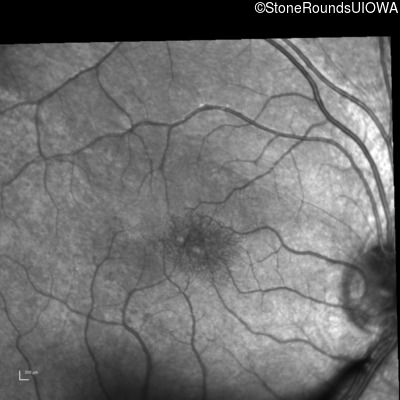

Infrared Fundus Photograph - Right - 20/40 -2

Exemplar